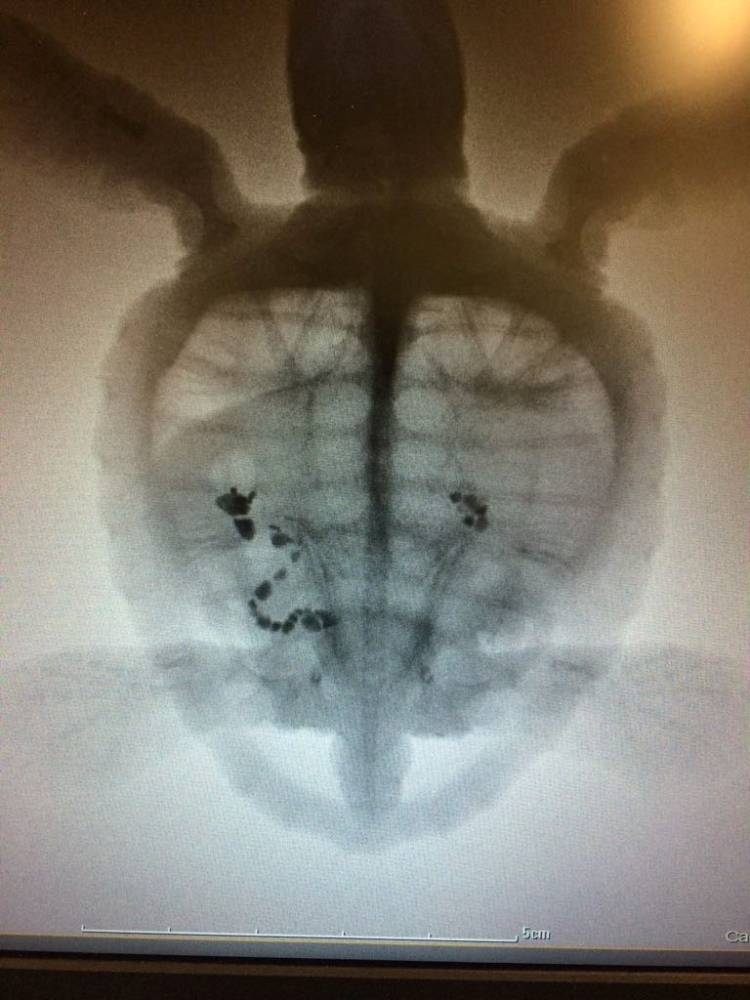

Tiny #10 has faced many difficulties since his arrival a few months ago. Weighing just 44g, he was an absolutly tiny hatchling. Although eating well, #10 was continuously losing weight and struggling to dive. You may remember that a hi-tech X-ray technique was used on him to examine his intestines when he was first brought to us.

Two Oceans Aquarium veterinarian Brandon Spolander had this to say: “#10 demonstrated some health issues from when first admitted. One of the concerns was with the functions of his intestinal tract. A detailed series of X-rays was undertaken, including contrast media studies over a period of 10 days. This demonstrated that there was an area of the lower intestine that was not functioning normally."

"Unfortunately this was not to be and although the hatchling did quite well for an initial period, he then became very lethargic and stopped eating. Follow-up X-rays at this point supported the theory that his intestine was blocked and not functioning as it should. Due to the poor success rates of this type of surgery it was elected to euthanise this small turtle rather than have him experience any further suffering."

Using a contrast fluid, we are able to use x-rays to examine the insides of these tiny hatchlings.